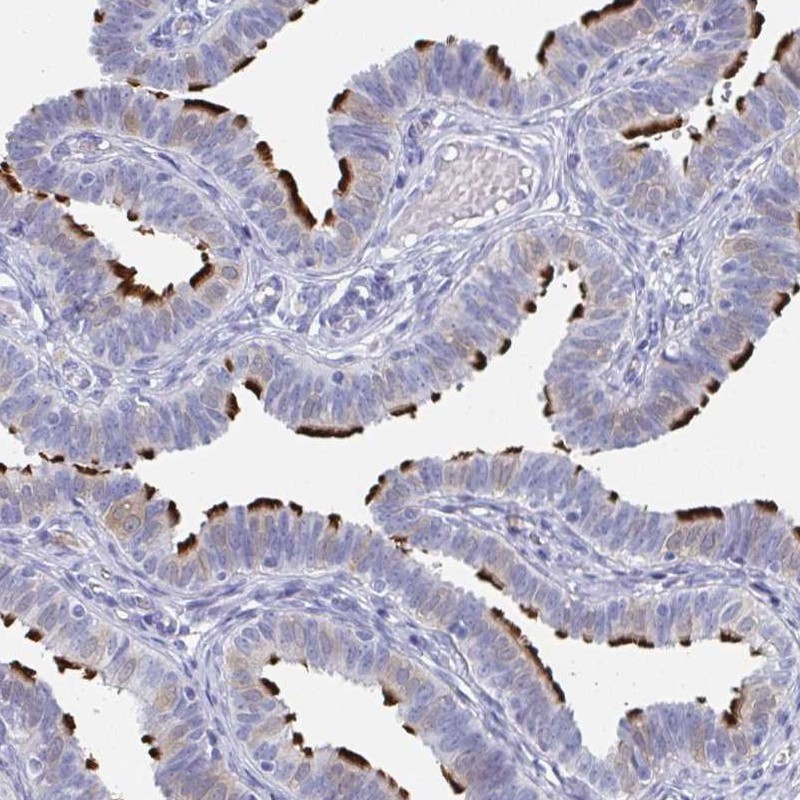

Immunohistochemistry analysis in human fallopian tube and tonsil tissues using Anti-DYDC2 antibody. Corresponding DYDC2 RNA-seq data are presented for the same tissues.